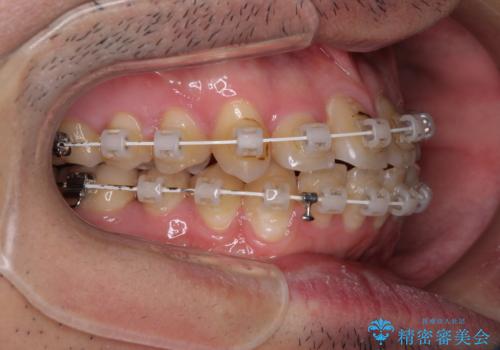

- 審美装置

マウスピース矯正での自己管理には自信がないとのことで、ワイヤー装置による矯正治療を行うこととしました。